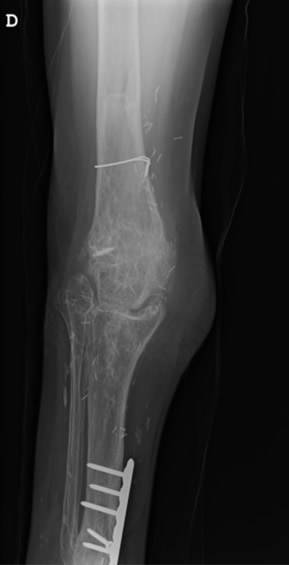

Diagnóstico: Prótesis oncológica de rodilla infectada y expuesta

Paciente de 41 años con antecedentes de osteosarcoma de rodilla previamente intervenida con una prótesis oncológica. La prótesis está infectada, expuesta y en una extremidad lesionada por la radioterapia. La amputación es el único tratamiento que le han recomendado.

- Megaprótesis oncológica de rodilla infectada

- Defecto masivo articular con exposición de la prótesis

Paso 1: Retirada de prótesis, espaciador y cobertura estable

Retirada de la prótesis infectada. Colocación de espaciador de metacrilato con antibióticos y cobertura del defecto con transferencia microvascular ALT.

Paso 2: Retirada del espaciador y reconstrucción de rodilla con articulación del tobillo

Paso 3: Reconstrucción del defecto de tobillo con peroné microvascular

03. Resultado

El resultado funcional fue excelente con preservación de la pierna. La paciente pudo caminar a los 20 meses de la intervención. Una técnica única desarrollada por el Dr. Cavadas que permite evitar la amputación en casos extremos de prótesis oncológica infectada.